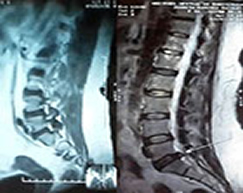

" Que tu Medicina sea tu Alimento, y el Alimento tu Medicina " ... Hipócrates " Somos lo que comemos " ... Feuerbach " Una Dieta Sana y Ejercicio, favorecen una Vejez Saludable " Tratamiento de Origen Natural Nuestra prestación de Servicios de Salud a nivel profesional en Medicina son otorgados en forma individual por cada uno de Nosotros, y ayudan principalmente en los siguientes Padecimientos: HERNIA DE DISCO o HERNIA DISCAL DE COLUMNA VERTEBRAL OSTEOARTRITIS DEGENERATIVA o ARTROSIS ( Osteoartrosis - Degeneración del Cartílago de las Articulaciones ) OSTEOPOROSIS y OSTEOPENIA ( Descalcificación y Desmineralización de los Huesos ) ARTRITIS REUMATOIDE o REUMÁTICA. ENVEJECIMIENTO PREMATURO GONARTROSIS ( Gonartritis Degenerativa - Degeneración de Meniscos y Cartílagos de las Rodillas ) y también en:

CIÁTICA LUMBALGIA ( Lumbago - Dolores de Espalda ) MIGRAÑA ( Cefaleas - Dolores de Cabeza ) FRACTURAS DE COLUMNA VERTEBRAL y otras PADECIMIENTOS DEL ADULTO MAYOR y ENVEJECIMIENTO

Folleto del Tratamiento Romacel  ¡ Vea, descargue, comparta y distribuya el FOLLETO FLYER publicitario, explicativo del Tratamiento Romacel con tooo el resumen y ejemplos de los Casos Clínicos resueltos ... Hernia Discal de Columna Vertebral, Artrosis degenerativa, Osteoporosis y Osteopenia, Artritis Reumatoide, Gonartrosis de Rodillas, Ciática y Lumbalgia, entre otras ... ... y Si lo desea, Sea un Distribuidor Independiente y forme parte del Grupo Romacel Internacional en su Ciudad, Estado y País, para ayudar a las personas de su Comunidad !  ¡ Vea los Casos Clínicos resueltos !

¡ Observe algunos ejemplos de los Casos Clínicos desde el 2007 que han sido resueltos satisfactoriamente !

¡ Regenere, Fortalezca, Prevenga y Evite una Cirugía de su Columna Vertebral, Rodillas y Articulaciones !